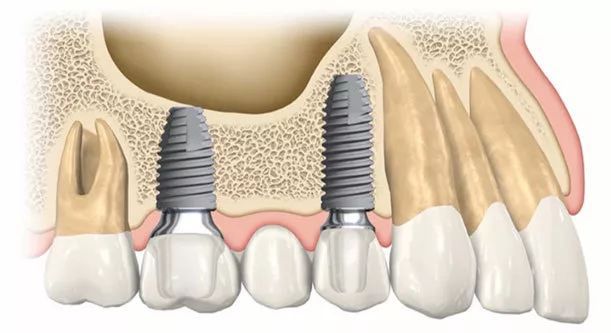

種植牙是一種現代化的修復缺失牙齒的方法。與傳統的義齒相比,種植牙具有更好的外觀、穩定性和功能性。不過,種植牙需要考慮一些條件,確保術後效果和健康保障。

首先,牙周疾病要得到控制。對於有牙周疾病的患者,需首先進行治療,以達到口腔健康的狀態。牙周疾病包括牙齦炎、牙周炎等,如果不加控制,可能導致牙周組織受損,影響種植牙的穩定性和成功率。

其次,口腔狀況要符合種植牙的要求。牙齦、唾液等都會對種植牙產生影響。如果牙齦出現腫脹、萎縮等問題,需要在種植前進行相應的修復。此外,唾液分泌不足、口腔乾燥等情況也會對種植牙的生長產生不利影響。

第四,種植牙前要進行全面檢查。口腔醫生會通過拍X光片、CT掃描等多種方式來瞭解牙齒、骨質及周圍組織的狀態、位置和密度等資訊,並制定相應的手術方案。